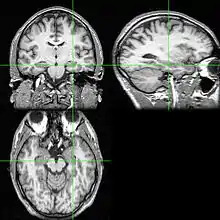

Imbalances found in certain serotonin receptor activity in cortical association regions, including the frontal lobes, are found in individuals with AN and may be the cause of impairment in their working memory, attention, motivation, and concentration.[31][32] In addition, the ability of individuals with AN to activate remote memories, learn new information, plan ahead, regulate actions according to environmental stimuli, and shift behavioural sets appropriately are all implicated.[31] Some individuals with anorexia nervosa (AN) have an inability to change their pattern response behaviours, which has been linked to disturbances found in the cortical and subgenual cingulate - mesial temporal pathways of these individuals.[31]

The reduced blood flow in the limbic system of individuals with AN is what mostly accounts for their impairment in cognitive functioning.[33] More specifically, the set of structures in the limbic system including the temporal lobes and adjacent structures like the hypothalamus, amygdala, and hippocampus are important in memory as well as emotion, appetite regulation, motivation, and perception, and are therefore implicated.[33] Reduced cerebral blood flow to these areas have also been associated with impairments in complex visual memory, enhanced information processing and visuospatial ability.[34]

Individuals with AN have been reported to have prolonged exposure to high levels of corticosteroids, a class of chemicals involved in things such as stress and behaviour,[35] and prolonged exposure to corticosteroids has been associated with impairments in memory and learning.[35][36][37][38][39] The hippocampus is an area of the brain that is dense with corticosteroid receptors, and therefore may be what is mediating these impairments.[36][37][38][39][40][41][42]